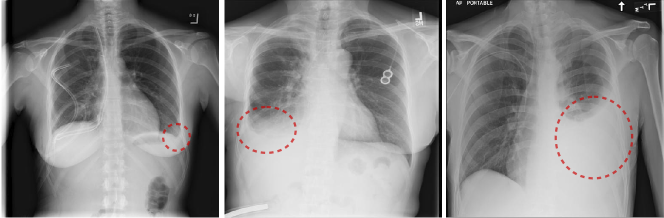

Figure 1: Left: small left pleural effusion. Middle: moderate right effusion. Right: large left pleural effusion.

In addition to the disease labels that represent the presence or absence of certain disease, we also want to utilize the attributes of those diseases contained in the radiology reports. Disease severity level (DSL) is one of the most critical attributes, since different severity levels are correlated with highly different visual appearances in chest X-rays (see examples in Fig. 1). Radiologists tend to state such disease severity levels (i.e., [minimal, tiny, small, mild], [middle-size, moderate], [remarkable, large, severe], etc.) when describing the findings in chest X-rays. This type of disease attribute information can be exploited to enhance and enrich the accuracy of NLP-mined disease labels, which consequently may facilitate to build more accurate and robust disease classification and localization framework than [11]. More recently, Wang et al.  [12] proposed the TieNet (Text-Image Embedding Network), which was an end-to-end CNN-RNN architecture for learning to embed visual images and text reports for image classification and report generation. However, the disease attributes were not explicitly modeled in the TieNet framework.